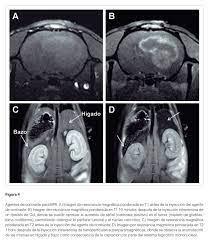

En la resonancia magnética, se detectan las propiedades magnéticas de las moléculas. Durante la hiperpolarización, estas propiedades se amplifican significativamente durante un cierto período, lo que da como resultado una señal mucho más fuerte de lo habitual. Biológicamente, las moléculas se comportan como antes. Por lo tanto, los procesos metabólicos se pueden observar de forma no invasiva. Este método es seguro, no requiere radiación y la RM metabólica solo toma unos minutos.

2. Con los agentes de contraste biológicos altamente sensibles desarrollados, la conversión de piruvato en lactato y alanina se demostró con éxito en un modelo animal. Estas conversiones en el metabolismo energético ya se han identificado como marcadores diagnósticos útiles en estudios previos.